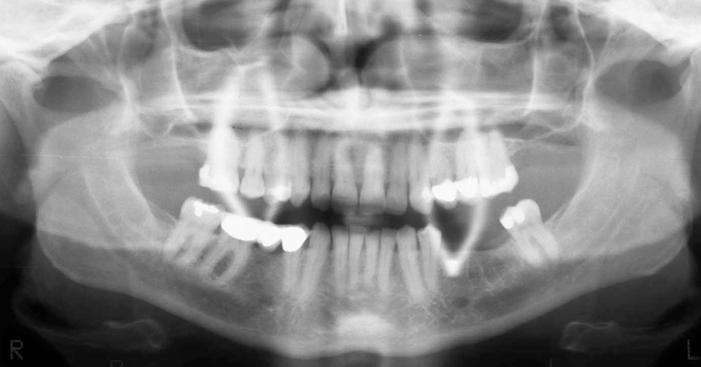

What is wrong with this image?

A

earrings